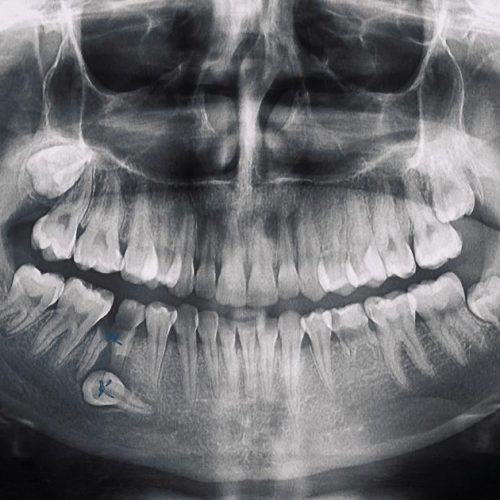

İmplant Tedavisi Ne Kadar Sürer?

Eğer ki Hastanın kemik yapısı uygun ise İmplant uygulaması aynı gün içerisinde yapılabilir.

İmplant Fiyatı Nedir?

İmplant Fiyatları için hemen bizimle iletişime geçebilirsiniz. İmplant Fiyatları 300 Euro'dan başlamaktadır.